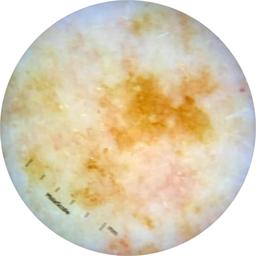

ISIC_9965024

Clinical

Field Value

acquisition_day 129

age_approx 75

anatom_site_1 Head and neck

anatom_site_general head/neck

concomitant_biopsy False

diagnosis_1 Benign

diagnosis_confirm_type single image expert consensus

family_hx_mm False

image_manipulation instrument only

image_type dermoscopic

lesion_id IL_4355888

patient_id IP_7946204

personal_hx_mm True

sex female